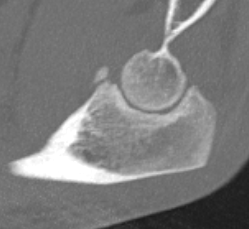

Approach through radial head, suture fixation and repair over button

Medial approach and screw fixation